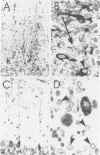

Rabies virus is a highly neuronotropic virus and glial cell infection is not prominent in the central nervous system (CNS). Paraffin-embedded tissues from the cerebella of skunks experimentally infected with either a skunk salivary gland isolate of street rabies virus or the challenge virus standard (CVS) strain of fixed rabies virus were examined with immunoperoxidase staining for rabies virus antigen by using an anti-rabies virus nucleocapsid protein monoclonal antibody. A skunk infected with street rabies virus showed prominent infection of Bergmann glia. Although infected Purkinje cells were observed, they usually demonstrated a relatively small amount of antigen in their perikarya. A CVS-infected skunk showed many intensely labeled Purkinje cells and a relatively small number of infected Bergmann glia. These findings indicate that although rabies virus is a highly neuronotropic virus, street rabies virus strains do not always demonstrate strict neuronotropism in the central nervous system.